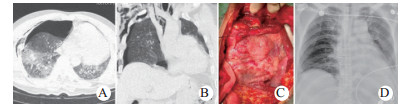

| 图 3 例5伤后9 d心包疝嵌顿,松解和心脏复位术(A、B:术前CT示心包疝嵌顿和左移; C:术中见心肌挫伤后肉芽期; D:术后3 d胸部X线平片示心脏已复位) Fig 3 Case 5 showed incarceration of pericardial hernia, decompression and cardiac reduction on 9 days after injury(A and B: Preoperative CT showed incarceration and left shift of pericardial hernia; C: The granulation stage after myocardial contusion observed during the operation; D: The chest X-ray showed the restored heart on postoperative day 3) |

有研究在体外循环下作心脏修复[4],但笔者赞同非体外循环下手术,理由为:手术分秒必争,体外循环的运行耗费时间; 患者常有多发伤,肝素化可成致命威胁; 心脏修补多可非体外循环下完成。手术入路有报道中用胸骨正中劈开[4],而笔者更多用左前外侧切口。不同于疾病治疗,体外循环建立和心内直视手术均需胸骨正中劈开; 心脏创伤需分秒必争迅速进胸。心肌或心包破裂多在前壁即右室和左侧,易经左前外侧切口处理,必要时横断胸骨或劈开上段; 费时的胸骨劈开减少获救机会。手术主要为心包减压、控制出血、心脏按压复跳、破口修补、心包积血清除、心包疝和脱位扭转的复位固定、心包开窗引流等。心肌破裂多数现场死于大量血胸或心脏压塞。破裂部位发生率依次为右室、左室、右房、左房; 心房破裂较心室破裂获救机会多[3, 6, 14-15]。非全层破裂心脏压塞后易自限出血。喷血的心肌破口指压下先作一针控制缝合,确切修补后再将其拆除。破口较大用Foley尿管送入堵住出血再修补。应警惕多个破口,发现后壁破口时用小纱块暂时填塞,将患者改侧卧位延长为后外侧切口,后壁变侧壁即易操作。心包疝箝闭是心包破裂的危急并发症,患者可迅速死于心源性休克,破向左侧较多[5, 8]。膈心包破裂可致心包膈疝,引起心脏压塞。心包疝还纳后,因心肌肿胀心包缝合困难时可用补片。病情危重则敞开心包,分离箝闭性黏连; 若将心脏向中线复位固定困难,术后取疝出反方向卧位1周,使心脏在较好位置黏连固定(图 3D)。经胸膜腔手术不放置心包引流管,膈神经后心包开窗和安放胸腔引流管可明显减少心搏干扰及心包、心内感染机会。